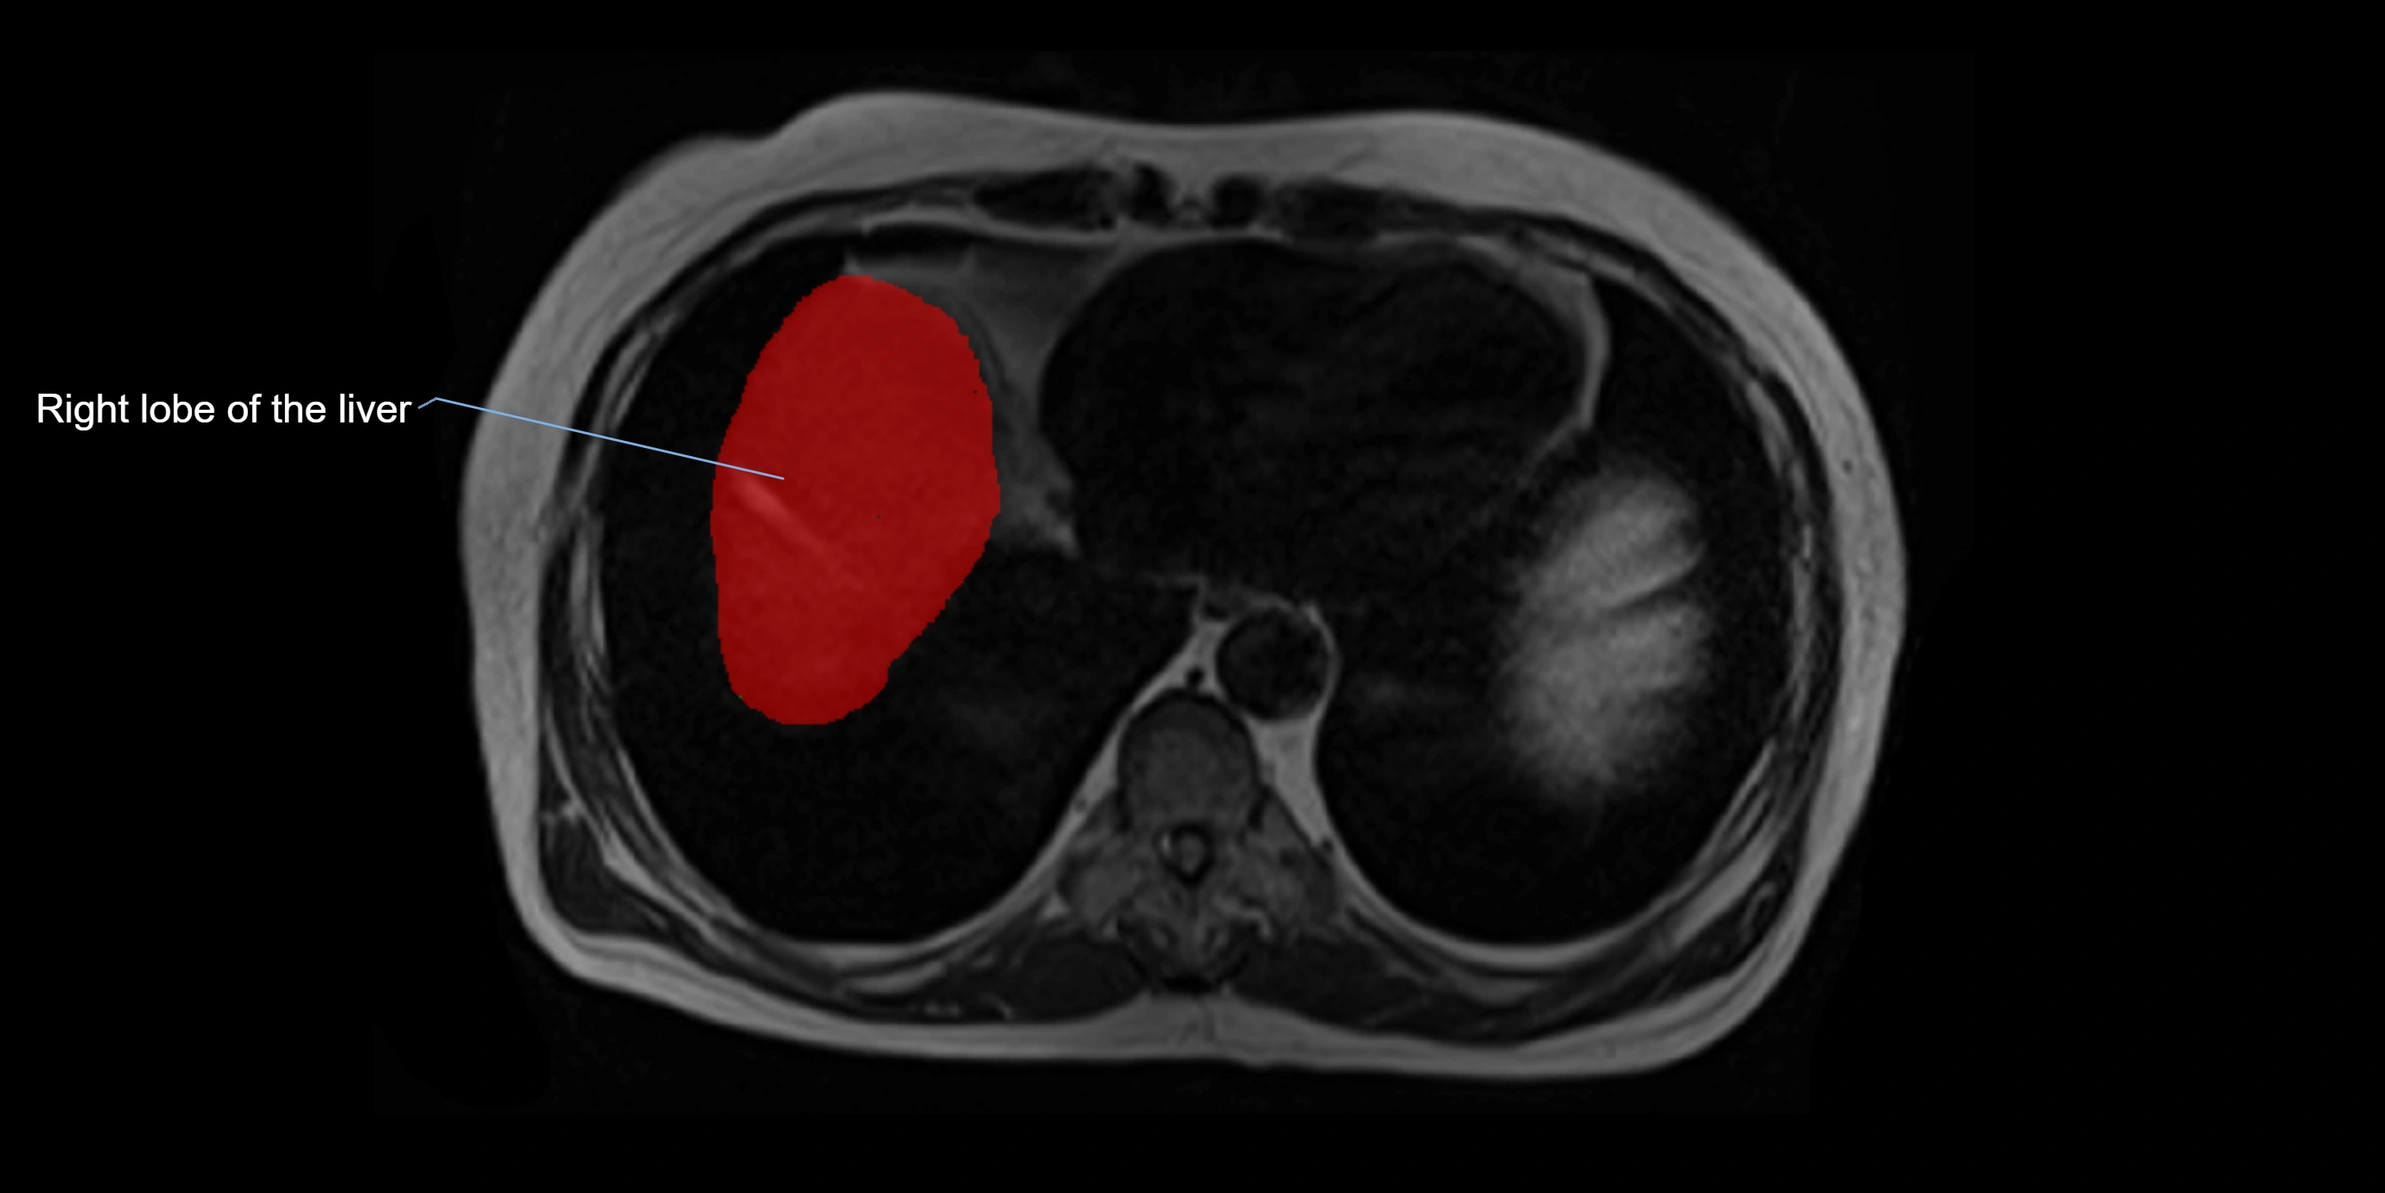

The caudate lobe of the liver is a distinct anatomical subdivision of the liver, designated as segment I in Couinaud’s classification. It lies on the posterior surface of the liver, between the fissure for the ligamentum venosum (left boundary) and the groove for the inferior vena cava (IVC) (right boundary). Superiorly, it is related to the posterior liver surface, and inferiorly it is separated from the left lobe by the porta hepatis.

This anatomical autonomy makes the caudate lobe especially significant in liver surgery, transplantation, and hepatic venous outflow obstruction syndromes (e.g., Budd–Chiari syndrome). Enlargement of the caudate lobe is a characteristic imaging feature in chronic liver disease and cirrhosis.